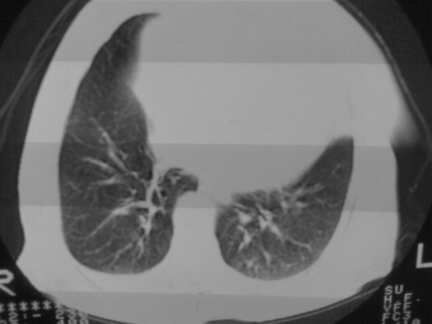

标题: CT13142:女 80 胸闷、气短、1w [打印本页]

标题: CT13142:女 80 胸闷、气短、1w

右肺炎性变

右肺感染;双侧胸腔少量积液,心影增大,可能与心功不全有关;胸内甲状腺肿。

胸内甲状腺肿;右肺感染;双侧胸腔少量积液。

胸内甲状腺肿;右肺中叶感染;双侧胸腔少量积液;心影增大,考虑有心功能不全。